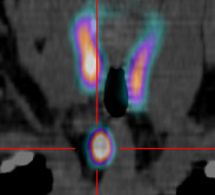

-Bilan étiologique d'une hyperparathyroïdie -Localisation préopératoire des adénomes parathyroïdiens -Recherche de glandes parathyroïdiennes pathologiques ectopiques.